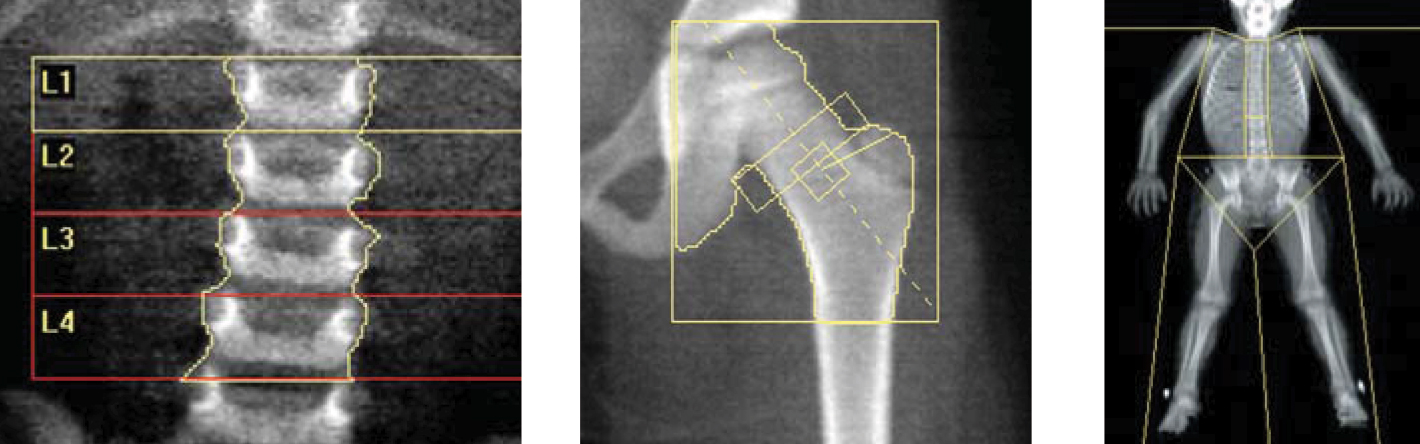

The test to measure bone mineral density is called bone densitometry. It is the most widely used method for bone density measurement today.

Bone density measurement is a very easy process. The system performs the measurement in a short time like 8 minutes while the person is lying on his back. In our clinic, bone density measurement is performed with our state-of-the-art General Electric/LUNAR brand device.

The most important diagnostic method is bone density measurement. The examination is done with a special device using a very low dose of x-rays. The procedure does not require preparation or medication, it takes a short time. Bone density measurement is carried out in our unit in 10-20 minutes, without any preliminary preparation, without any injection, with computer support.